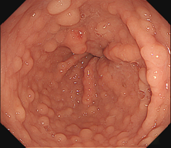

步骤六:为防止创面迟发性出血,可以使用金属夹子夹闭创面。本图为夹子在创面旁打开;

步骤七:金属夹子于创面处夹闭。